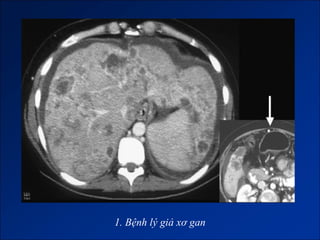

1. Bệnh lý giả xơ gan (Micmic cirrhosis).

1. Bệnh lý giả xơ gan

1. Bệnh lýgiả xơ gan

• #84 Bệnh lý giả xơ gan do - Congenital hepatic fibrosis (phì đại HPT I và thùy bên gan trái, teo gan phải, HPT IV bình thường) - Di căn từ ung thư tuyến vú (phì đại HPT I, bờ gan không đều) - U hạt ở gan (thường phải sinh thiêt). - HC Budd-Chiari (phì đại HPT I, dấu hiệu TALTMC, ).

• #85 Bệnh lý giả xơ gan do - Congenital hepatic fibrosis (phì đại HPT I và thùy bên gan trái, teo gan phải, HPT IV bình thường) - Di căn từ ung thư tuyến vú (phì đại HPT I, bờ gan không đều) - U hạt ở gan (thường phải sinh thiêt). - HC Budd-Chiari (phì đại HPT I, dấu hiệu TALTMC, ).